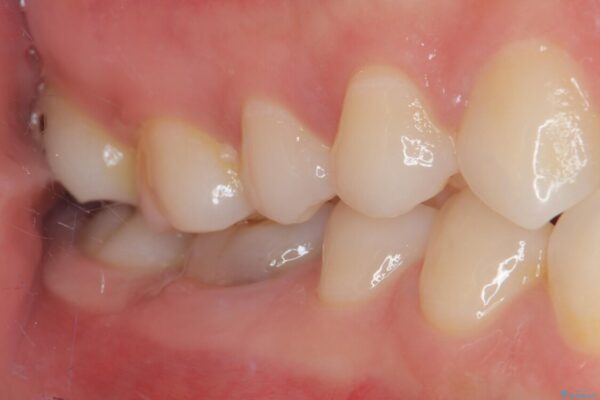

「以前に根管治療をした歯が、噛むと違和感がある」とのことでご来院された患者様の症例です。 患者様は、数年前に他院で根管治療を受けたとのことでしたが、被せもの(クラウン)は装着されていない状態でした。 噛んだときの違和感が慢性的にあり、食事中も気になるとのことで当院にご相談いただきました。 レントゲン検査では、根の先端に透過像(根尖病変の可能性)が見られ、過去の治療ではラバーダム防湿が使用されていなかったそうです。

治療前

• ラバーダム使用で再感染リスクを抑えた再根管治療+精密な補綴による長期安定を実現 治療前画像